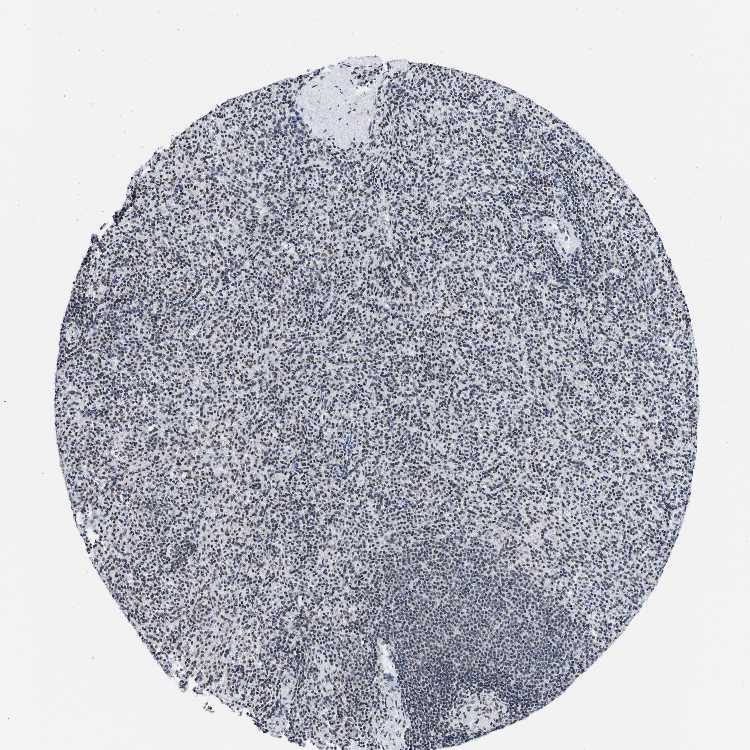

SPLEEN - Antibody stainingi

Antibody staining in the annotated cell types in the current human tissue is reported as not detected, low, medium, or high, based on conventional immunohistochemistry profiling in selected tissues. This score is based on the combination of the staining intensity and fraction of stained cells.

Each image is clickable and will lead to virtual microscopy that enables deeper exploration of all samples and also displays staining intensity scores, fraction scores and subcellular localization as well as patient and tissue information for each sample.

Antibody HPA018403

Cells in red pulp Medium

Cells in white pulp Medium